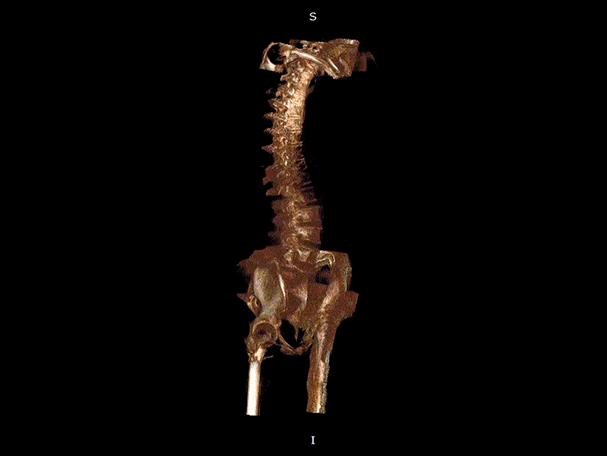

腰椎

VR体绘制重建